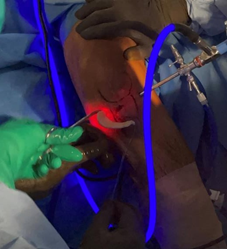

Location of portals

Standard anterolateral and anteromedial portals are made and the joint is visualized with a 30-degree arthroscope while the knee is insufflated with normal saline. A transpatellar accessory portal of the knee is made to facilitate fixation of the posterior horn. With the camera facing the posterior compartment, a spinal needle is inserted to estimate the best trajectory for soft tissue anchor insertion.